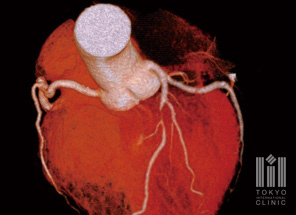

冠動脈の走行や狭窄を評価する「冠動脈CT検査」は、従来のカテーテル検査に比べて、身体的負担を大幅に軽減。体内をクリアな画像で立体的に読み取ることで、心臓の状態や働きを詳しく検査します。また、国内でもまだ導入施設の少ない米国PREMIER HEART社が開発した解析システム「MCG(心筋虚血診断検査)」も採用。これは心電図情報をデータ化し、インターネット経由で米国本社にある約4万人のデータベースと照合・解析することにより、心筋虚血の状態を診断できる画期的な検査手法です。

冠動脈CT/MRI検査

突然死の原因の1つである心筋梗塞のリスクとなる病変の早期発見に有効です